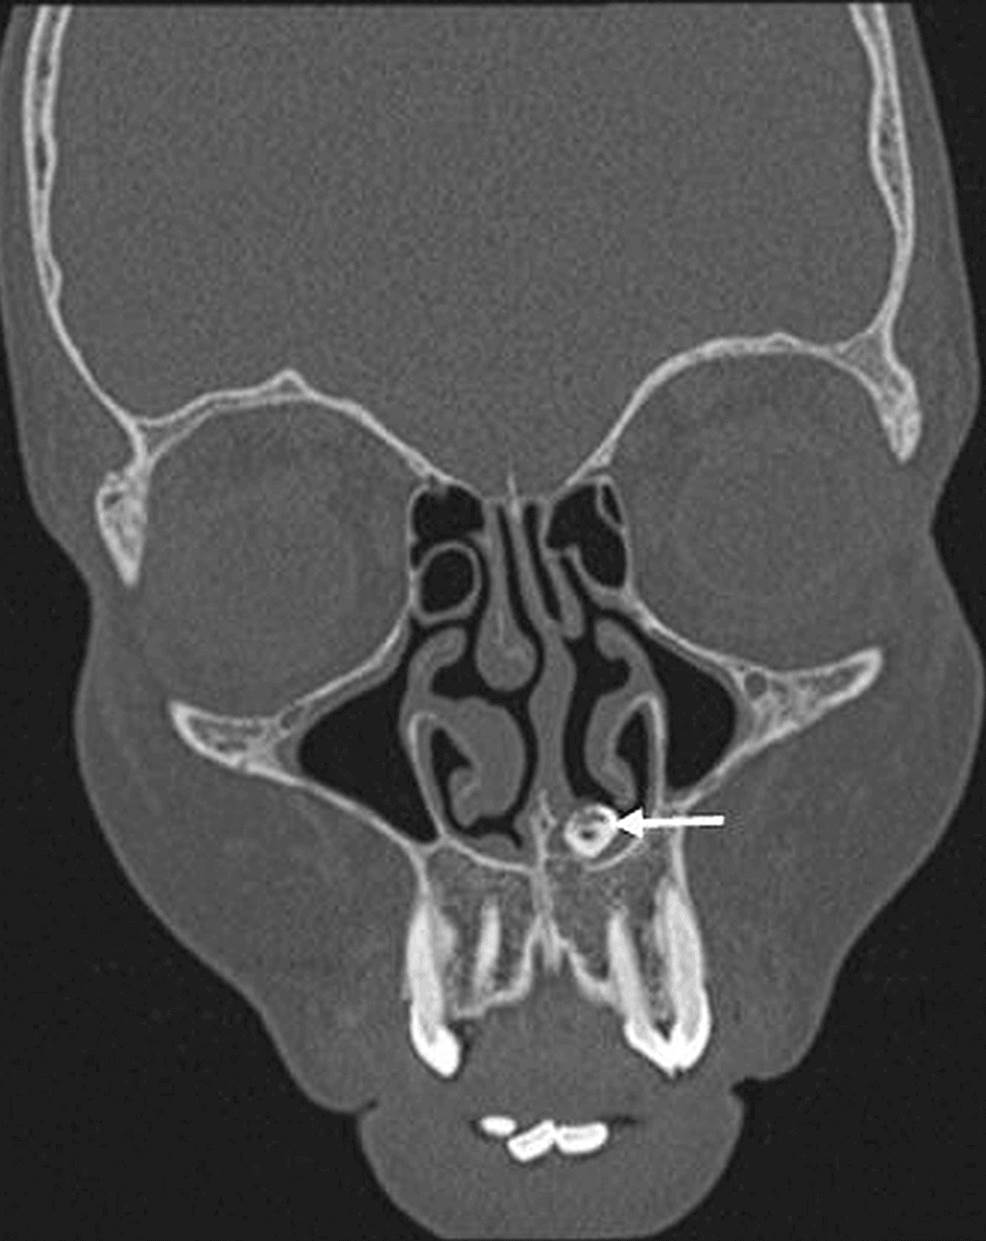

Recientemente, la literatura científica reportó que una paciente de 15 años se presentó con quejas de hiposmia y obstrucción nasal. El caso fue confirmado tras realizársele una tomografía de los senos paranasales y la cavidad nasal mostró una estructura similar a un diente en la cavidad nasal inferior izquierda que se extendía desde el paladar duro.

Raro de diente ectópico intranasal en mujer joven se registra en la literatura  Imagen coronal que muestra una estructura similar a un hueso (flecha blanca) incrustada en el paladar duro que se extiende hacia la cavidad nasal izquierda. Raro de diente ectópico intranasal en mujer joven se registra en la literatura  Tomografía computarizada axial que muestra un diente ectópico en la cavidad nasal izquierda rodeado de tejido blando (flecha blanca). Raro de diente ectópico intranasal en mujer joven se registra en la literatura  La radiografía simple muestra la estructura radiopaca en la fosa nasal izquierda, incrustada en el paladar duro (flecha blanca). Raro de diente ectópico intranasal en mujer joven se registra en la literatura  Imagen sagital que muestra la extensión completa de un diente intranasal (flecha blanca), que se encuentra incrustado en el paladar duro.

Recalcaron además la importancia de las imágenes radiológicas que ayudaron en el diagnóstico de un diente ectópico.